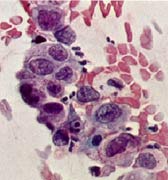

| Bei weiterer Veränderung an den Zellkernen kann es zu schweren Zellveränderungen kommen, die aber insgesamt noch keinen Krebs bedeuten, aber als unmittelbare Vorstufe dazu anzusehen sind. Hierbei muß meistens eine Gewebeprobe zur Abklärung entnommen werden (Grad IVa). | ![]() |

| Grad IVa | |